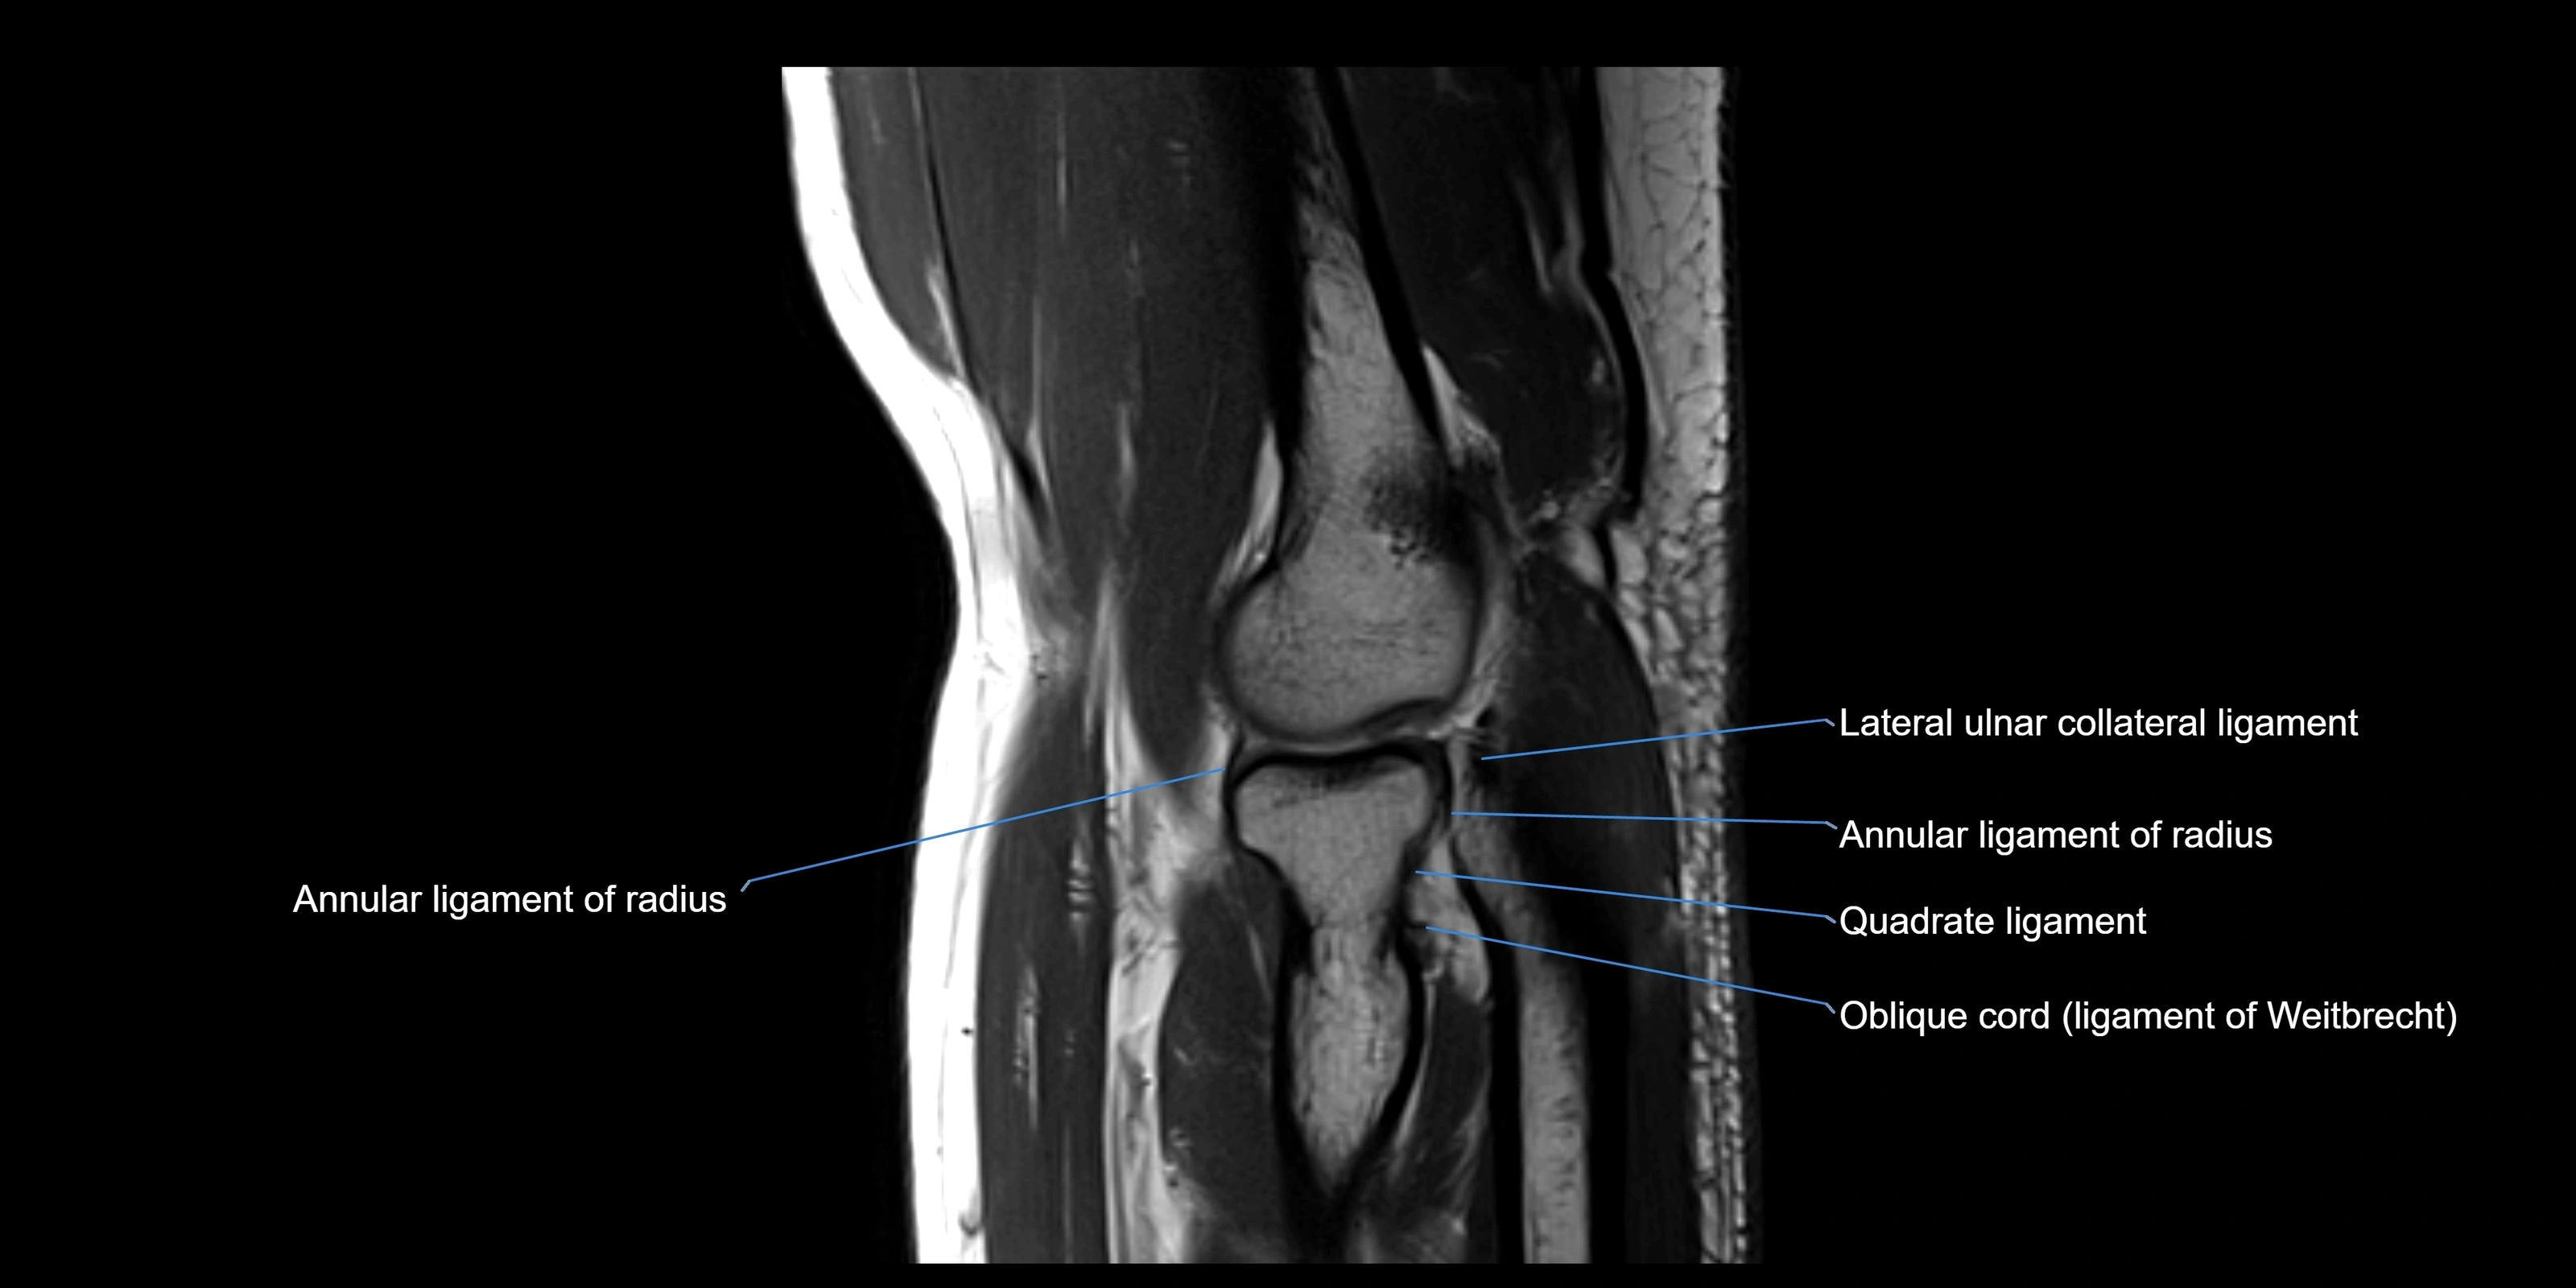

MRI images

image